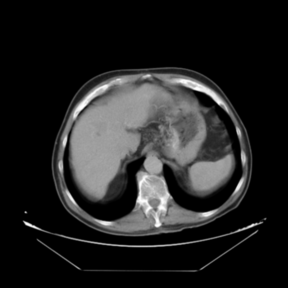

Figure 2. Spatial distances (in millimeters) between corresponding landmarks before and after the registration process

In addition to the previous measurements, the visual outcomes of two of the experiments are shown in Figures 3 and 4, whose purpose is to highlight the most illustrative differences (from a medical point of view) between the results provided by the compared methods. In Figure 3, we observe a normal size of the liver, with discretely irregular contours and homogeneous signal intensity. In hepatic segment II, there is a lesion of 40 mm of maximum axis, encapsulated and with well-defined contours and heterogeneous enhancement in arterial phase (after administration of intravenous contrast), suggestive of hepatocellular carcinoma (HCC). In this slice of the CT scan, we can also observe the aorta that shines in the arterial phase, the lower area of the stomach and the upper area of the spleen. In Figure 4, the liver has a normal size with discretely irregular contours in relation to changes due to chronic liver disease. In hepatic segment IV, a 36 mm diameter focal lesion is identified, which has arterial phase enhancement with a small area of necrosis of 13 mm; it corresponds to a HCC previously chemoembolized with partial necrosis. In this slice of CT, we can also observe the aorta, the gastric chamber and the spleen. When comparing the two methods under study, it can be seen how in Figure 3 the resulting registered datasets are very similar. However, looking closely, it can be noticed that in the right part of the image (left side of the patient) the shape and width of the structures corresponding to the stomach and the spleen in Figure 3(d) match better those in the reference dataset. Likewise, the part of the rib at the upper right of the image is more similar to the same region in the reference dataset by using the proposed method. Regarding the experiment shown in Figure 4, it can be easily appreciated how the geometrical matching (with respect to the reference dataset, Figure 4(a)) of the structures in the right side of the image (specially the gastric chamber) is visually more satisfactory in Figure 4(d). Moreover, the area of tumor necrosis which results from the proposed method is also slightly better aligned.

Arterial phase (reference dataset, R) Portal venous phase (template dataset, T)

(a) Arterial phase (reference dataset, Failed to parse (MathML with SVG or PNG fallback (recommended for modern browsers and accessibility tools): Invalid response ("Math extension cannot connect to Restbase.") from server "https://mathoid.scipedia.com/localhost/v1/":): {\textstyle R}

)

(b) Portal venous phase (template dataset, Failed to parse (MathML with SVG or PNG fallback (recommended for modern browsers and accessibility tools): Invalid response ("Math extension cannot connect to Restbase.") from server "https://mathoid.scipedia.com/localhost/v1/":): {\textstyle T}

Registered template, T_u (CR-based method) Registered template, T_u (proposed method)

(c) Registered template, Failed to parse (MathML with SVG or PNG fallback (recommended for modern browsers and accessibility tools): Invalid response ("Math extension cannot connect to Restbase.") from server "https://mathoid.scipedia.com/localhost/v1/":): {\textstyle T_\mathbf{u}}

(CR-based method)

(d) Registered template, Failed to parse (MathML with SVG or PNG fallback (recommended for modern browsers and accessibility tools): Invalid response ("Math extension cannot connect to Restbase.") from server "https://mathoid.scipedia.com/localhost/v1/":): {\textstyle T_\mathbf{u}}

(proposed method)

Figure 4. Visual outcomes of experiment 5 (slice 12): registration of arterial and portal venous phases of patient 2